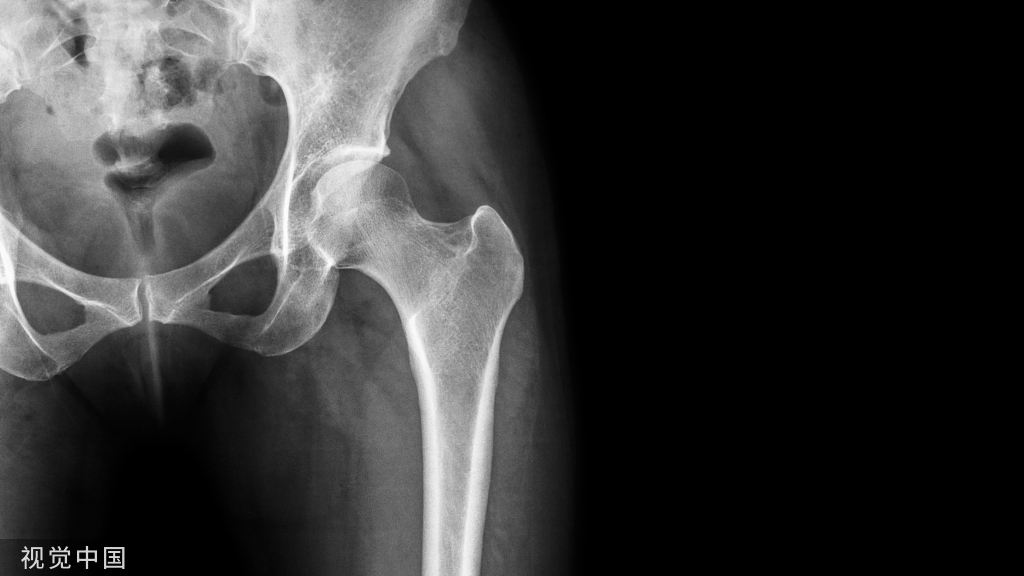

1.近端是最常见的,大部分的并发症都集中在了近端,主要是导致了切出、穿凿、内翻、退钉等。

头钉过短、内侧支撑不足、导致的6周出现内翻,最后肢体短缩2cm,出现这些的原因,意味着骨折不稳定!初始固定没有达到应该稳定骨折的效果